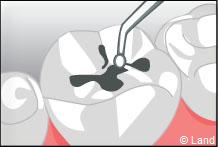

Les traitements possibles pour les stades de la carie où seuls l’émail et la dentine sont touchés peuvent se faire avec de l’amalgame qui est un matériau indiqué dans la restauration des petites et moyennes cavités.

L’amalgame est utilisé sous forme de capsules prédosées et avant son utilisation est préparé par un vibreur qui mélange les composants de façon homogène. Il se présente sous la forme d’une pâte, plastique qui durcit dans la cavité nettoyée de la lésion carieuse et devient pratiquement aussi résistant que les tissus dentaires.